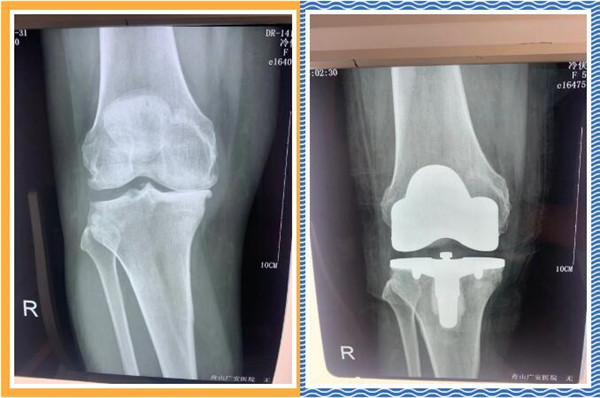

經(jīng)查體及拍片檢查后,危立軍副院長認為冷大姐是右膝關(guān)節(jié)嚴(yán)重磨損,是年輕時干重體力工作導(dǎo)致關(guān)節(jié)提前磨損,年紀(jì)是輕了一點,但關(guān)節(jié)置換是一種相對較好的辦法,可早期恢復(fù)關(guān)節(jié)正常,改善生活質(zhì)量,建議其入院并接受人工膝關(guān)節(jié)表面置換手術(shù)。。

三天后,冷大姐接受了右膝關(guān)節(jié)置換手術(shù)。手術(shù)由危立軍副院長主刀,在關(guān)節(jié)鏡下順利完成。術(shù)后,冷大姐恢復(fù)良好。同時,在經(jīng)過院部協(xié)商后,減免了冷大姐的部分手術(shù)費用和住院治療費用。出院那天,冷大姐熱淚盈眶,感謝的話說了又說。